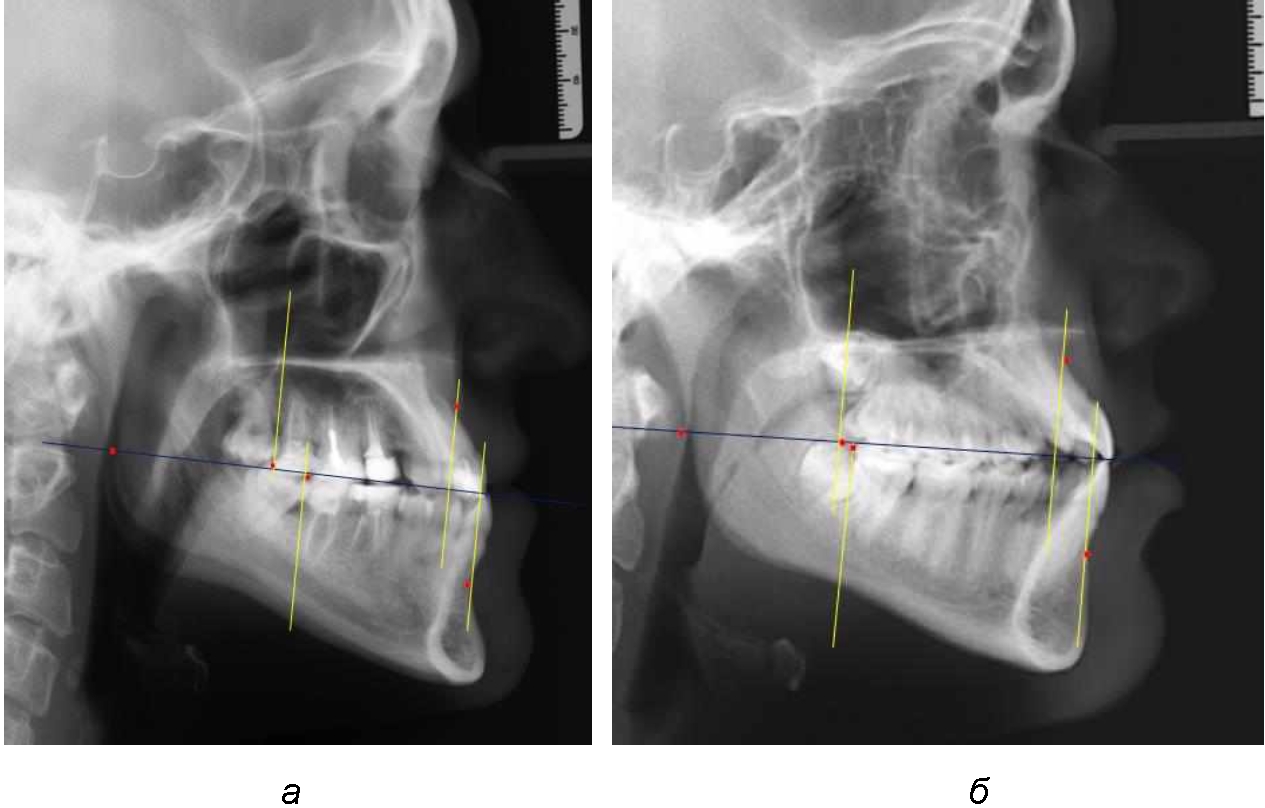

На рентенограммах с признаками дистальной окклюзии Wits-число имело положительные значения. Дистальная точка нижнего моляра была расположена позади верхней дистальной точки окклюзии второго моляра. Относительно равными, так же как и при анализе снимков с мезиальной окклюзией, считались показатели альвеолярно-дентальных размеров, при которых разница не превышала 1,5 мм. Тем не менее расстояние «rmРOcP-A(SS)» превышало расстояние «rmРOcP-B(SM)» в среднем по группе на (5,29 ± 1,47) мм (рис. 4).

Рис. 4. Положение апикальных точек и челюстей при дистальной окклюзии с равными (а) и разными (б) альвеолярно-дентальными размерами зубочелюстных дуг

В тех случаях, когда при дистальной окклюзии альвеолярно-дентальные размеры были различными, размер нижней челюсти превышал аналогичный параметр верхней челюсти, в среднем на (3,62 ± 1,12) мм.